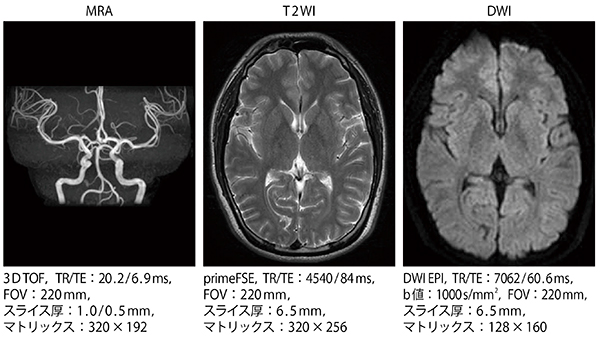

ECHELON OVAL によるMRI検査は,現在のところ脳ドックでのみ行われている。脳ドックでは,基本的にT1強調画像,T2強調画像,拡散強調画像,FLAIR,頭部MRA,頸部MRAを撮像しており,無症候性脳梗塞や未破裂動脈瘤,脳腫瘍,脳動脈奇形などの早期発見が期待される。読影を行う下野准教授は,なかでも動脈瘤検索のためのMRAの重要性を指摘する。

「検診では血管評価が重点の1つであるため,MRAの画質は重要です。3T装置と比べて,1.5T装置では,例えば大きく屈曲する内頸動脈サイフォンで信号が低下したり,血管が細長く描出されたりといったことをこれまで経験してきました。しかし,ECHELON OVALでは明瞭なMRAを撮像できており,動脈瘤検索において大きなメリットがあると感じています。また,MRA以外も限られた検査時間内できれいな画像が得られ,内耳道など微細な観察に用いるheavy T2強調画像も良好な画像を得られています」

■臨床例